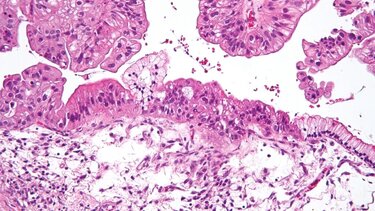

Όλες οι ασθενείς που συμμετείχαν στη δοκιμή είχαν χαμηλού βαθμού ορώδη καρκίνο των ωοθηκών, ο οποίος τείνει να προσβάλλει νεότερες γυναίκες.